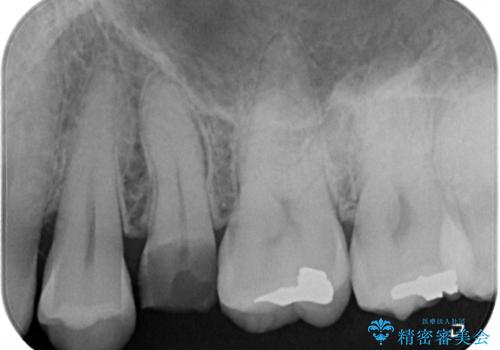

強い痛みのあった歯は、既に神経組織が失活しており根管治療が必要でした。

反対側の歯は、歯根だけが歯肉に埋もれて残っている状態のため、抜歯が必要な状態でした。

歯根だけとなっている歯はインプラントに、神経組織の失活している歯は根管治療を行い、いずれもオールセラミッククラウンにて補綴治療を行うこととしました。